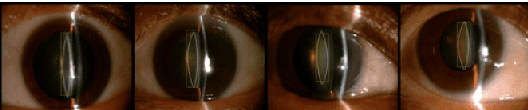

Abstract:Precise lens structure segmentation is essential for the design of intraocular lenses (IOLs) in cataract surgery. Existing deep segmentation networks typically weight all pixels equally under cross-entropy (CE) loss, overlooking the fact that sub-regions of lens structures are inhomogeneous (e.g., some regions perform better than others) and that boundary regions often suffer from poor segmentation calibration at the pixel level. Clinically, experts annotate different sub-regions of lens structures with varying confidence levels, considering factors such as sub-region proportions, ambiguous boundaries, and lens structure shapes. Motivated by this observation, we propose an Adaptive Confidence-Wise (ACW) loss to group each lens structure sub-region into different confidence sub-regions via a confidence threshold from the unique region aspect, aiming to exploit the potential of expert annotation confidence prior. Specifically, ACW clusters each target region into low-confidence and high-confidence groups and then applies a region-weighted loss to reweigh each confidence group. Moreover, we design an adaptive confidence threshold optimization algorithm to adjust the confidence threshold of ACW dynamically. Additionally, to better quantify the miscalibration errors in boundary region segmentation, we propose a new metric, termed Boundary Expected Calibration Error (BECE). Extensive experiments on a clinical lens structure AS-OCT dataset and other multi-structure datasets demonstrate that our ACW significantly outperforms competitive segmentation loss methods across different deep segmentation networks (e.g., MedSAM). Notably, our method surpasses CE with 6.13% IoU gain, 4.33% DSC increase, and 4.79% BECE reduction in lens structure segmentation under U-Net. The code of this paper is available at https://github.com/XiaoLing12138/Adaptive-Confidence-Wise-Loss.

Abstract:Cataract is one of the leading causes of reversible visual impairment and blindness globally. Over the years, researchers have achieved significant progress in developing state-of-the-art artificial intelligence techniques for automatic cataract classification and grading, helping clinicians prevent and treat cataract in time. This paper provides a comprehensive survey of recent advances in machine learning for cataract classification and grading based on ophthalmic images. We summarize existing literature from two research directions: conventional machine learning techniques and deep learning techniques. This paper also provides insights into existing works of both merits and limitations. In addition, we discuss several challenges of automatic cataract classification and grading based on machine learning techniques and present possible solutions to these challenges for future research.